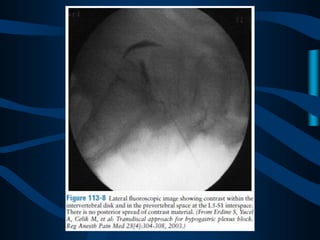

ABORDAJE

TRANSDISCAL

CON UNA AGUJA